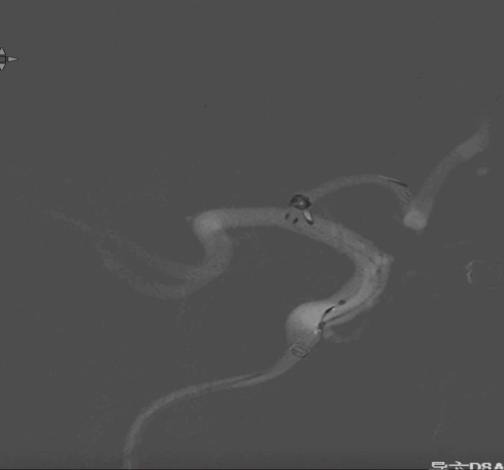

术后正侧位造影:Raymond Ⅲ级

术后支架重建:支架打开良好,近端Marker位于颈内动脉分叉处

术后Vaso CT未见出血,患者神清语利,神经系统查体阴性。